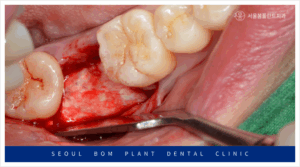

오금역치과 서울봄플란트에서는 임플란트 식립 전,

부족한 잇몸뼈를 채우기 위해

다량의 뼈이식을 먼저 진행하였습니다.

뼈이식은 임플란트를 안정적으로 식립하기 위한

필수적인 과정으로, 잇몸뼈가 부족한 경우에

필요한 치료입니다.

뼈이식 후에는 하얀색 막인 흡수성

멤브레인으로 이식한 부위를 덮어주었습니다.

이 흡수성 멤브레인은 이식한 뼈가

유실되지 않도록 단단하게 잡아주며,

뼈가 단단하게 굳는 동안

그 자리를 보호하는 중요한 역할을 합니다.

이 멤브레인은 골 형성 보조 기능을 담당하며,

차후 임플란트 식립 시 성공률을

더욱 높여주는 역할을 하게 됩니다.

뼈가 제대로 형성되기 위해서는

외부 자극이나 압력에 의한 손상을

방지해야 하므로, 이 멤브레인이

중요한 보호막 역할을 하는데요.

결국, 흡수성 멤브레인은 임플란트 식립 전후의

뼈 건강에 중요한 기여를 하며,

임플란트가 안정적으로 자리 잡을 수 있도록 돕습니다.